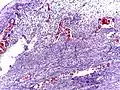

Pathology diagnosis of appendicitis can be made by detecting a neutrophilic infiltrate of the muscularis propria.

Periappendicitis (inflammation of tissues around the appendix) is often found in conjunction with other abdominal pathology.[71]

Micrograph of appendicitis and periappendicitis. H&E stain

Micrograph of appendicitis and periappendicitis. H&E stain Micrograph of appendicitis showing neutrophils in the muscularis propria. H&E stain